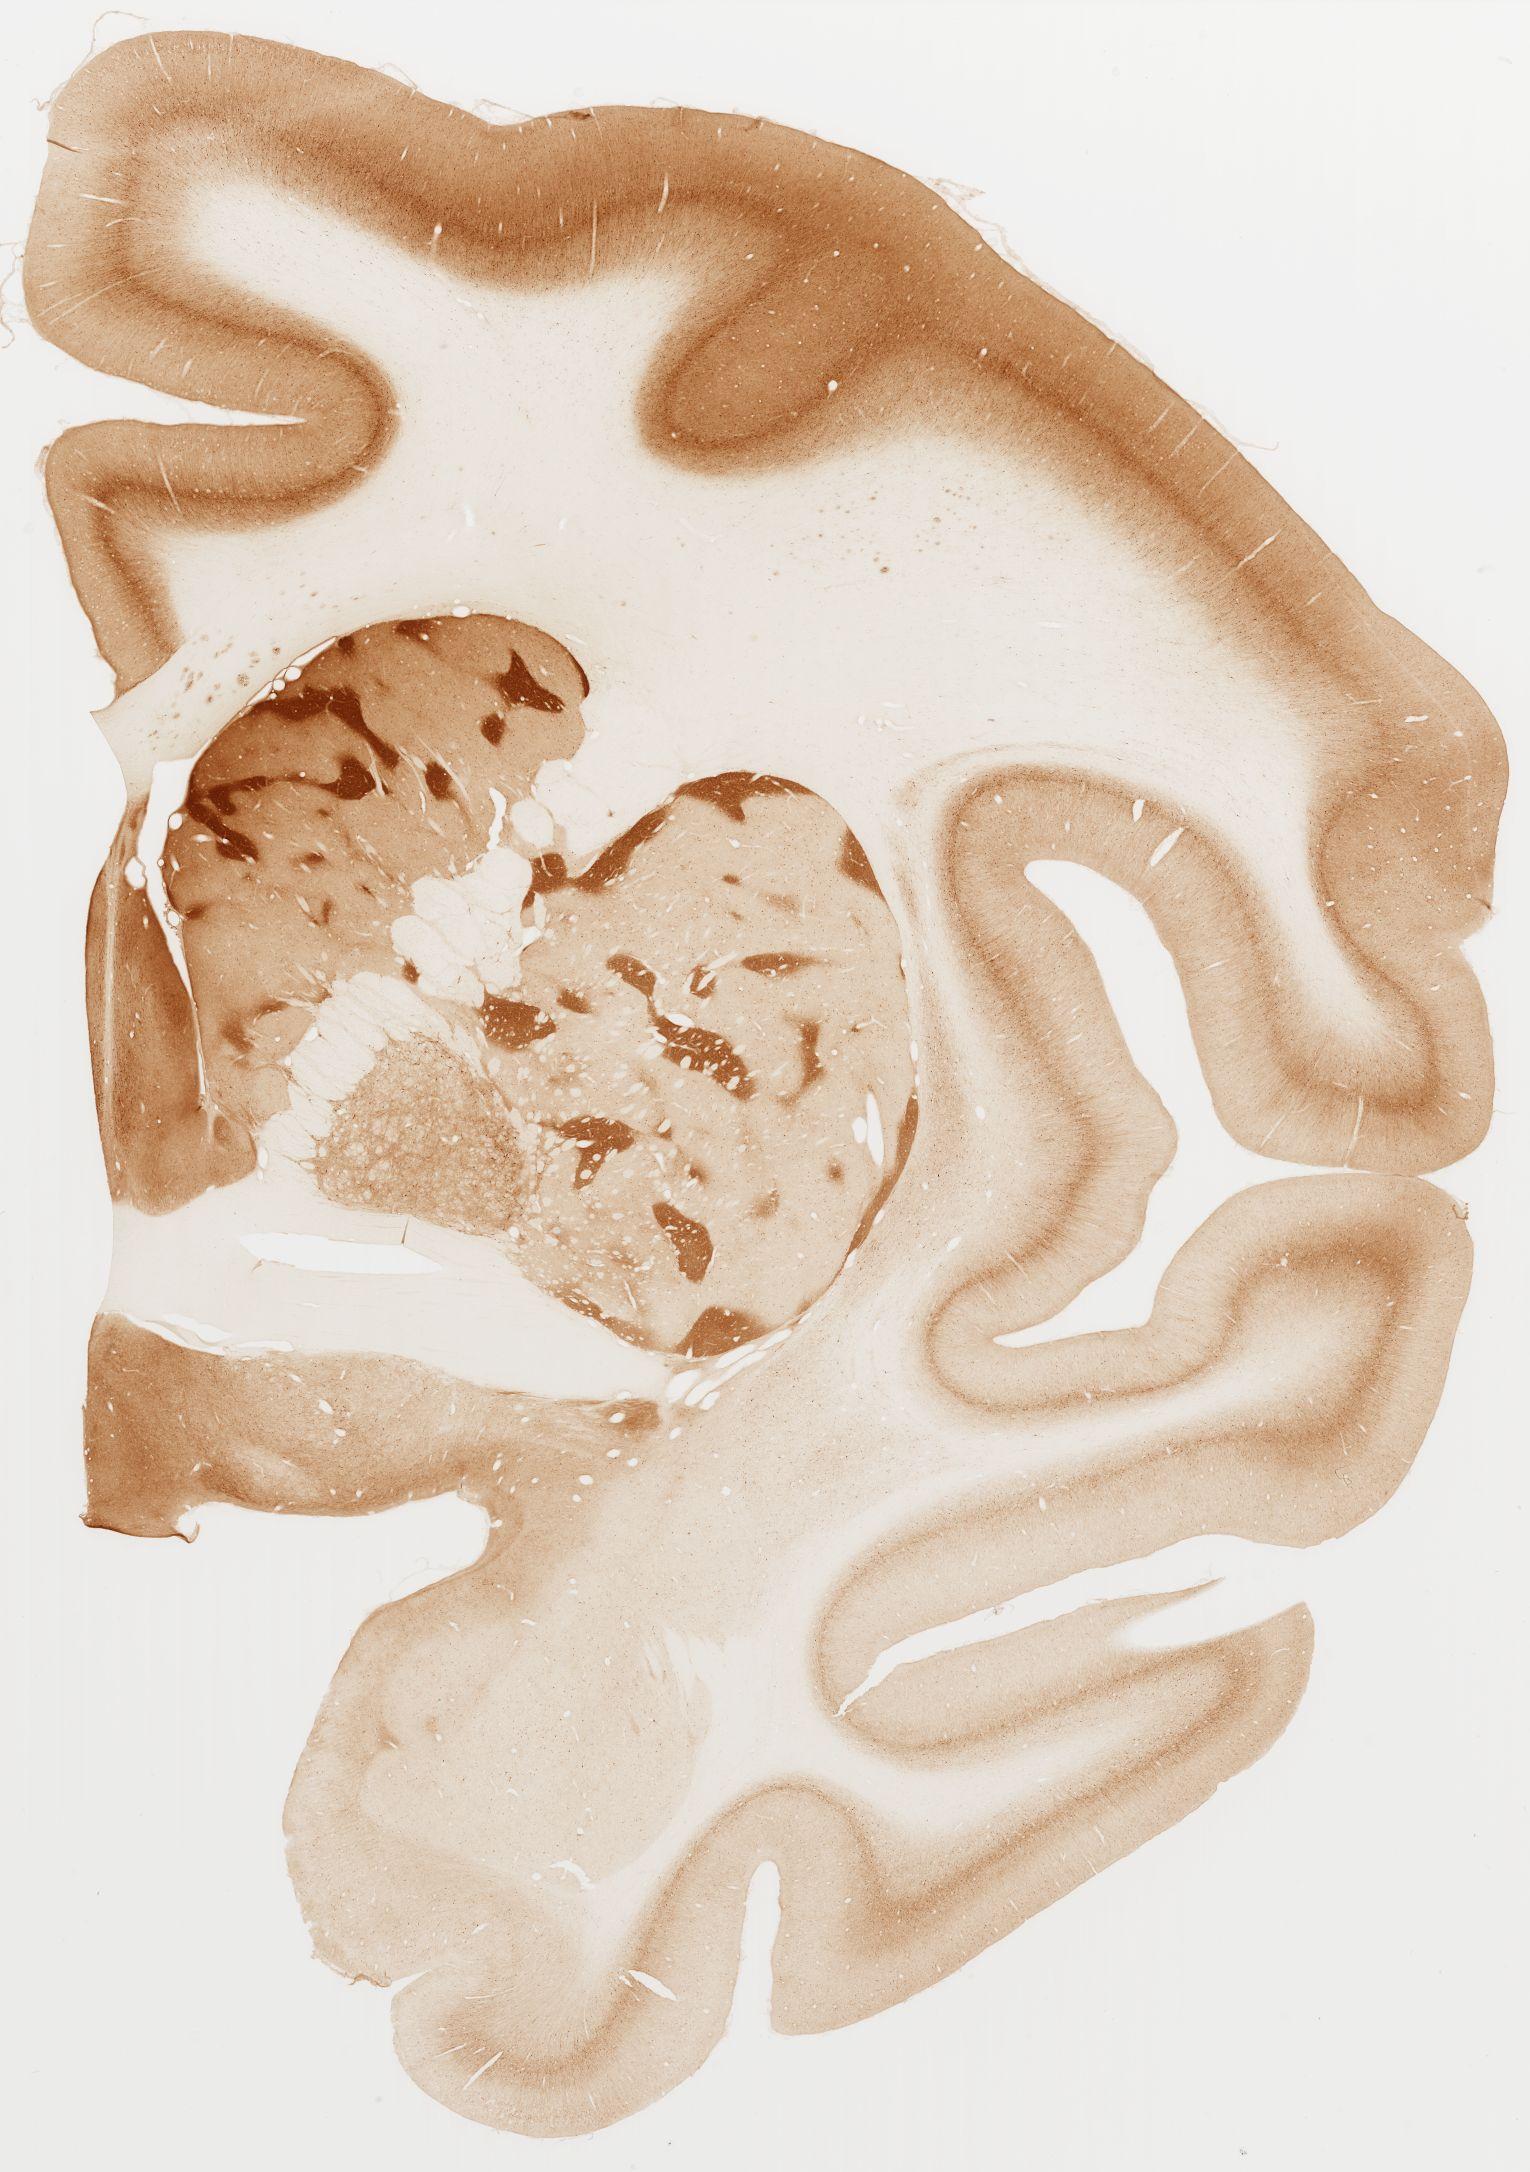

Datasets -> Macaca Fascicularis -> KChIP1, (Potassium Voltage-Gated Channel-Interacting Protein 1), coronal, immuno, Whole-Brain, adult

[ Metadata ]   ·   Source: Edward G. Jones

Displaying Sections 41 thru 80 of 92 Sections for this Dataset